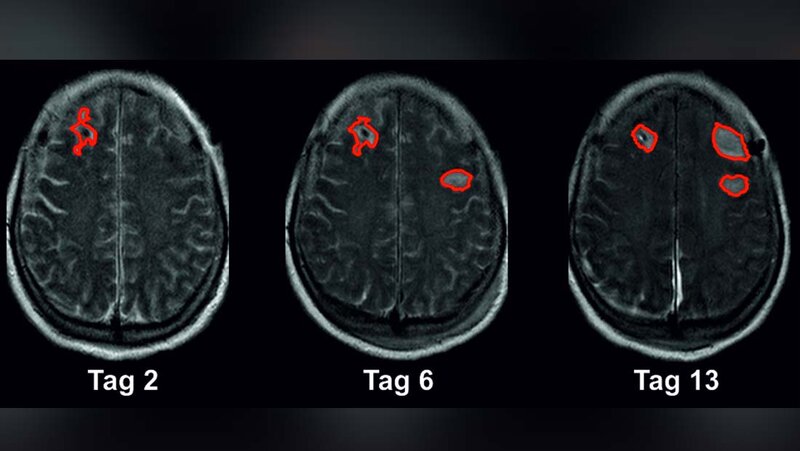

„Eine wissenschaftliche Erkenntnis der vergangenen Jahre ist jedoch zentral“, betont Prof. Dreier: „Die Entladungswelle ist bis zu einem gewissen Grad reversibel. Das bedeutet also, dass sich die Nervenzellen auch wieder erholen können, wenn das Nervengewebe rechtzeitig durchblutet und so mit Sauerstoff versorgt wird.“ Hier setzt die vorliegende klinische Studie, die an fünf verschiedenen Universitätskliniken durchgeführt wurde, an. Um die Spreading Depolarizations präzise zu messen, nutzten die Forschenden die Elektrokortikografie, ein Verfahren der modernen Neurointensivmedizin zur elektrodiagnostischen Überwachung der Gehirnströme. Dafür wurden den Betroffenen mit Subarachnoidalblutung bei Klinikeinweisung Elektroden unter die harte Hirnhaut implantiert. Zusätzlich verwendeten die Wissenschaftlerinnen und Wissenschaftler bildgebende Methoden wie Magnetresonanztomografie (MRT) und Computertomografie (CT). Sie werteten insgesamt rund 1.000 Bilder des Gehirns von 180 Patientinnen und Patienten mit Subarachnoidalblutung aus. In dieser bislang größten klinischen Studie zu Spreading Depolarizations konnten sie feststellen, dass durchschnittlich 46 Milliliter Hirngewebe in der Frühphase verloren gehen, also bereits, wenn die Betroffenen in die Klinik kommen. Weitere durchschnittlich 36 Milliliter werden in den ersten zwei Wochen beschädigt, während sich die Patientin oder der Patient in intensivmedizinischer Behandlung befindet.